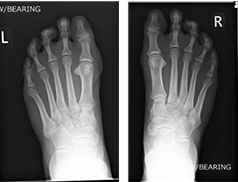

Weight-bearing X-ray (Left) and (Right)Weight-bearing X-ray (Left) and (Right)

The symptoms were attributed to overload metatarsalgia due to congenitally short first metatarsal bones in both feet. MRI and X-ray investigations can be seen at the right. The report verified there was no bone or joint signal typical of bone stress (or synovitis). Signal consistent with inter-metatarsal bursitis between the 2nd to 3rd inter-metatarsal space (indicated by yellow arrows). X-rays show very slight clawed second toes.